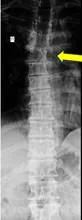

Боль в грудной клетке может быть вызвана остеохондрозом позвоночника, фасеточной (суставной) болью при деформации позвоночника. Например, при сколиозе (рентген ниже, желтая стрелка).